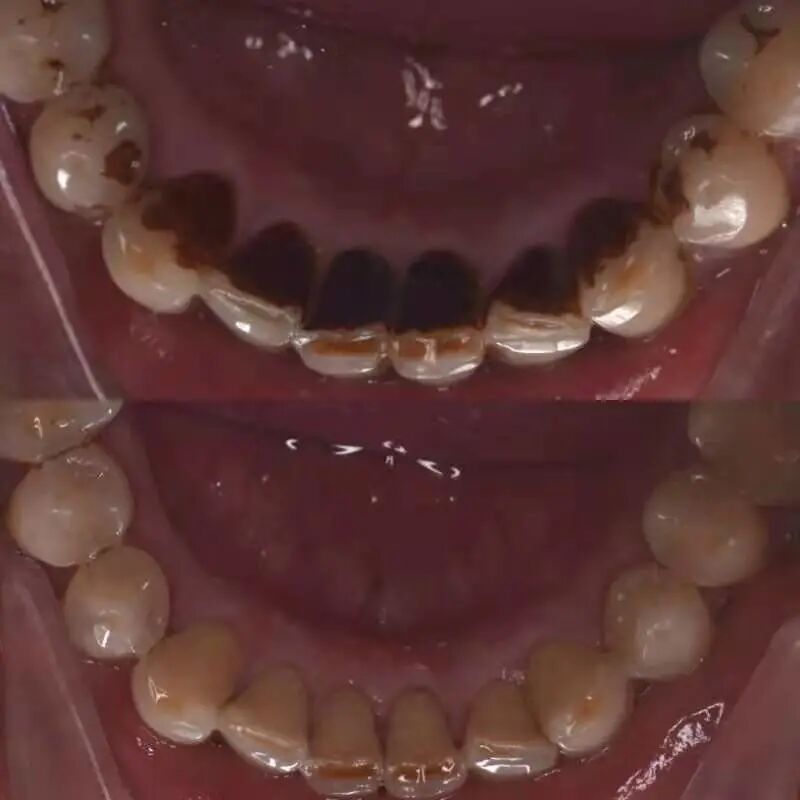

洗牙能让牙齿看上去变白

是因为洗掉了喝茶和咖啡、吸烟等留下的色斑

但白成一道闪电是不可能的

(洗牙将烟斑清除干净。作者供图)